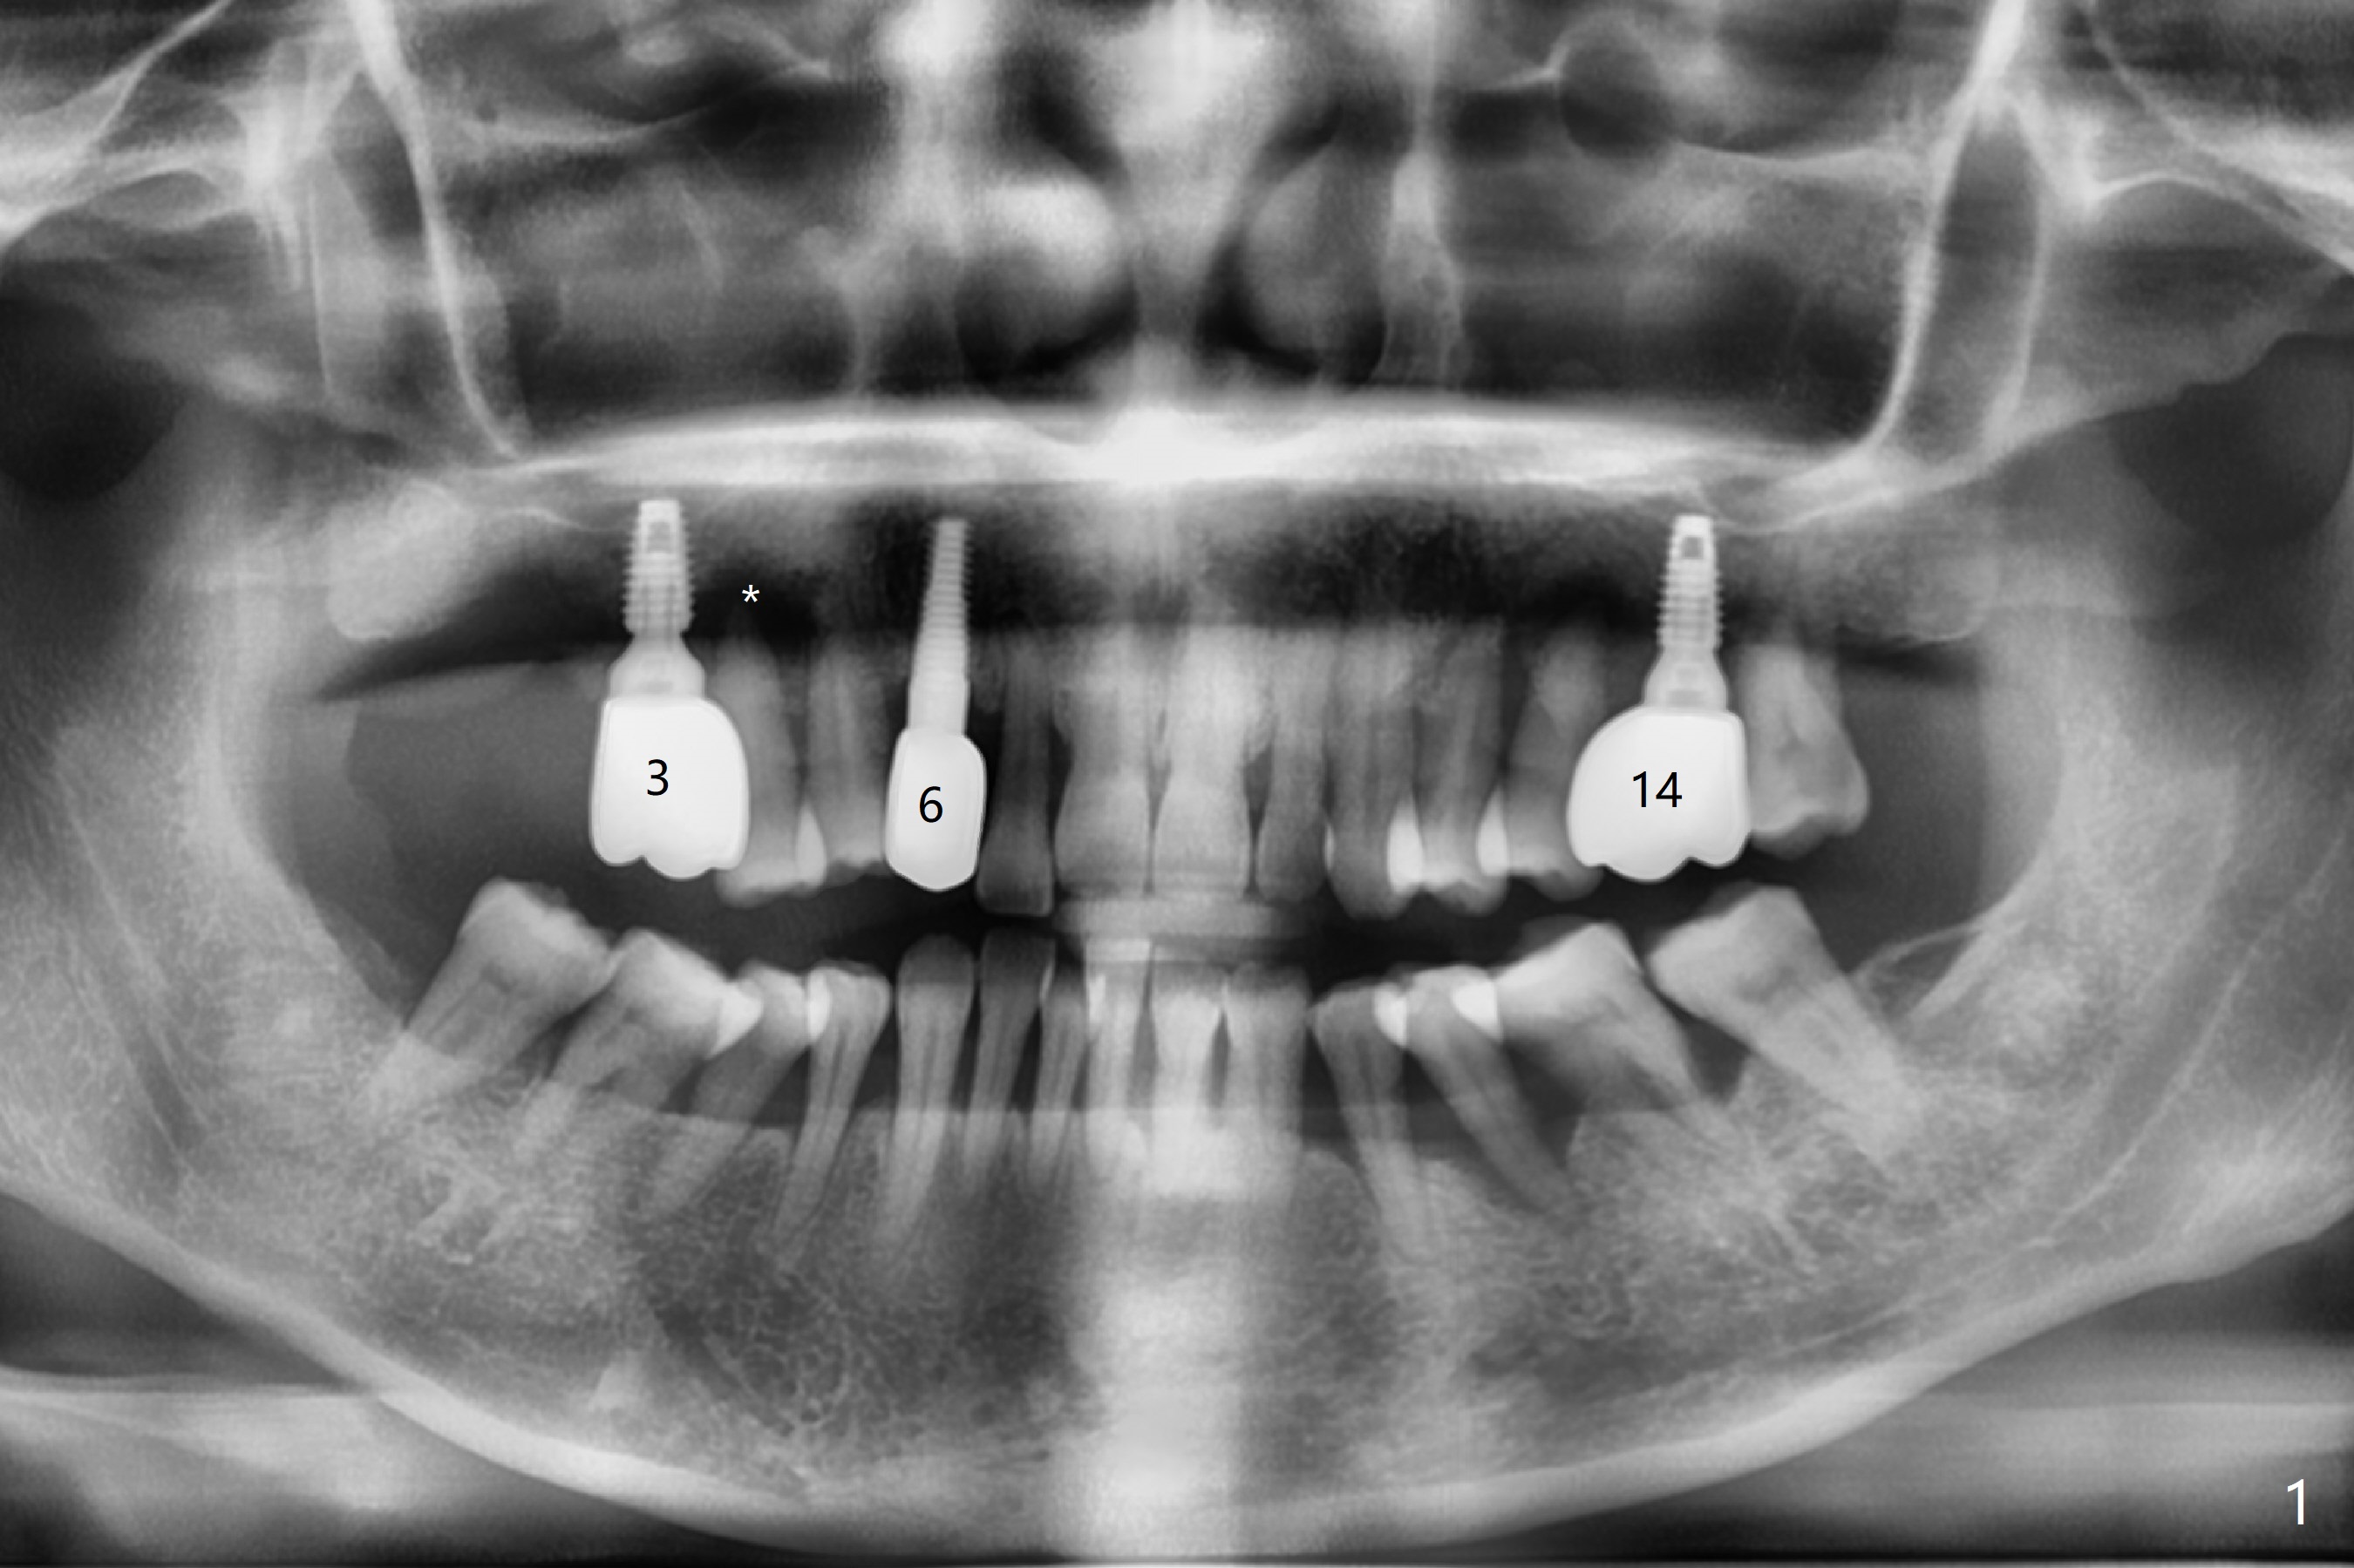

Implant